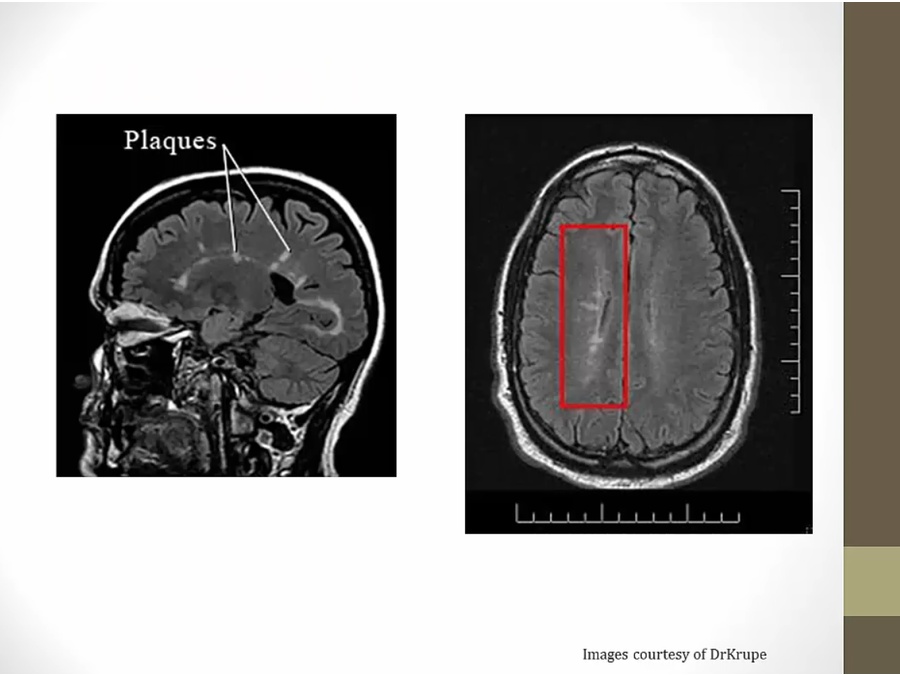

40 Demyelinating Diseases

MS